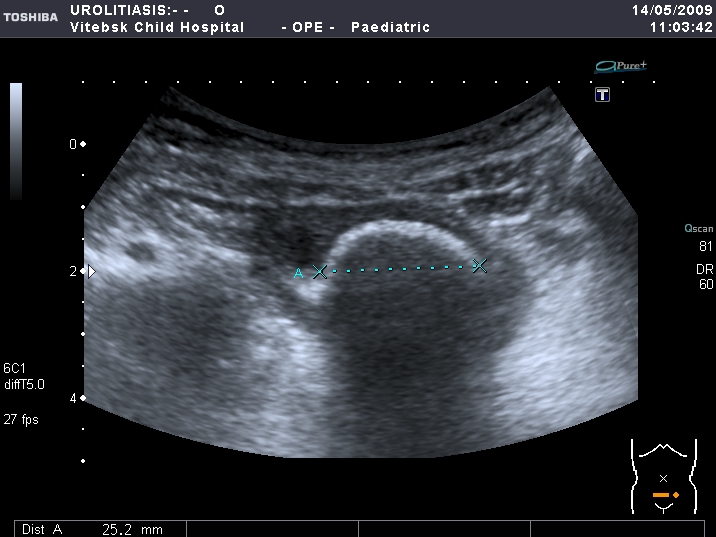

Сокращённый мочевой пузырь

Он же в поперечном скане

Если честно, и я изначально не совсем понял, где находится конкремент (а это конечно же конкремент), локализованный на урограммах. При первичном исследовании на УЗИ его я не видел (либо он спрятался за тенью конкремента мочевого пузыря, либо я обрадовался редкой находке конкремента такого размера в мочевом пузыре - 2.5 см, и не посмотрел что ниже). Тем не менее при ретроспективном анализе архивированных сонограмм, как мне кажется, он попал в один из сканов, м.б. не совсем чётко.

I20111114160229796.jpg

И всё -же, где конкремент :?: